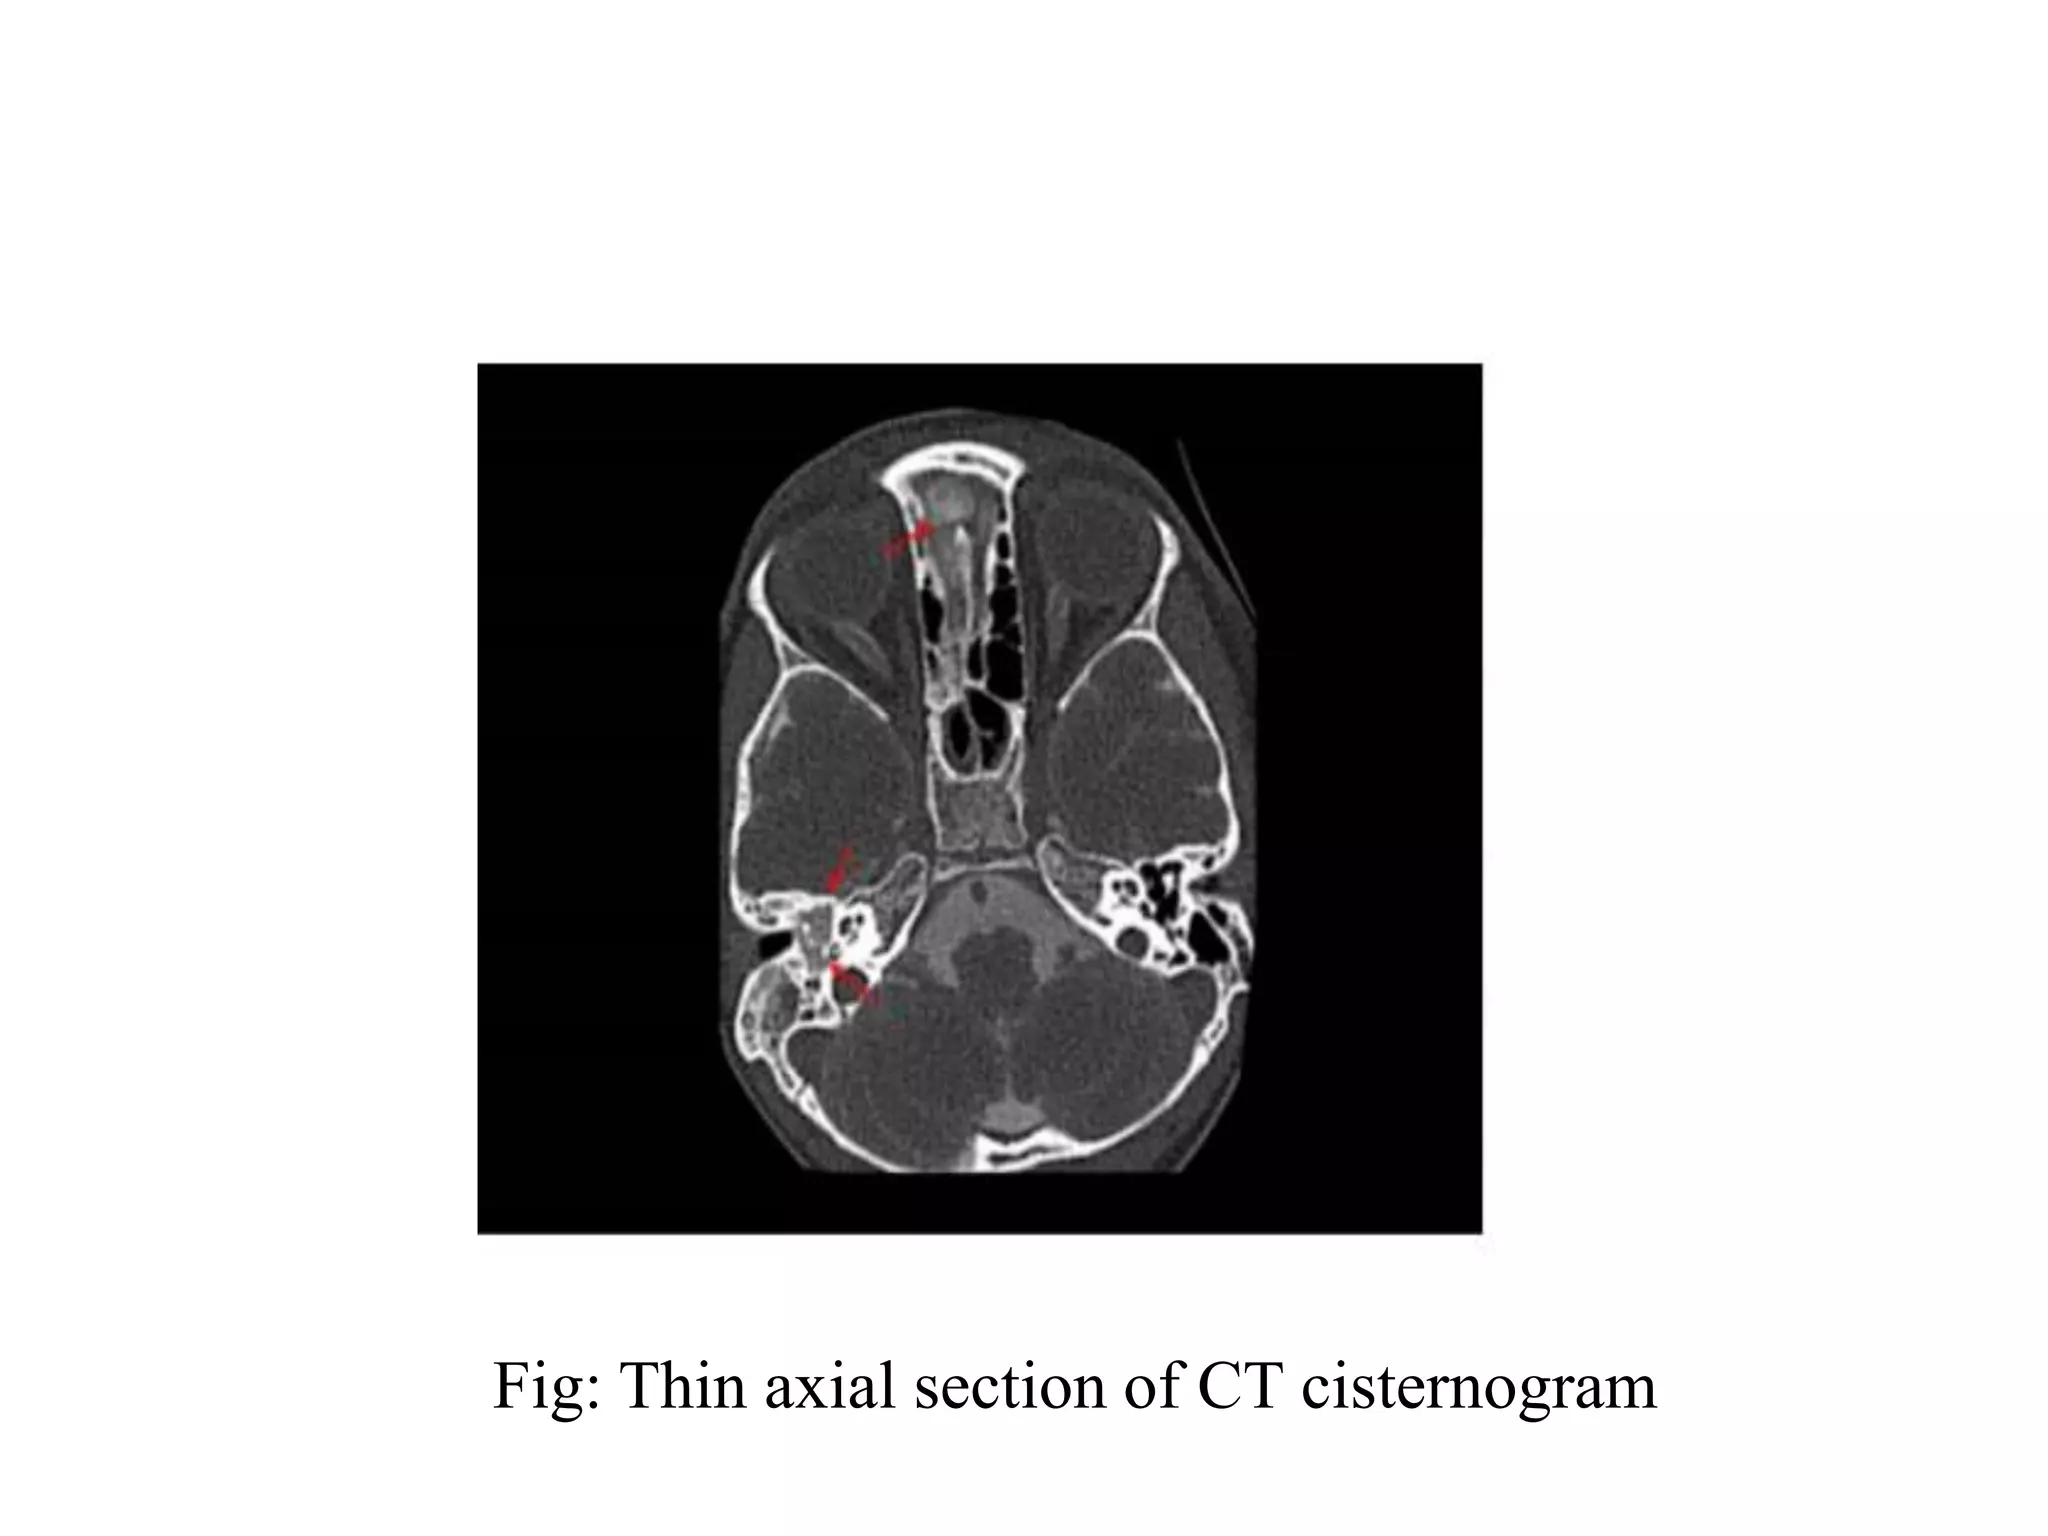

Fig: Thin axial section of CT cisternogram

Fig: Thin axialsection of CT cisternogram